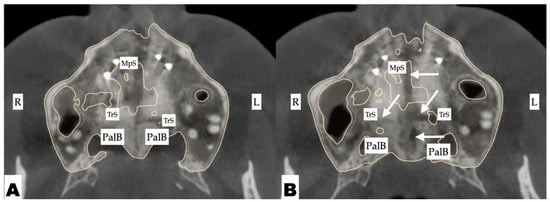

2.3.1. Surgical Protocol

2.3.2. Design of 3D Surgical Guide

2.3.3. Osteotomy Planning and Appliance Design